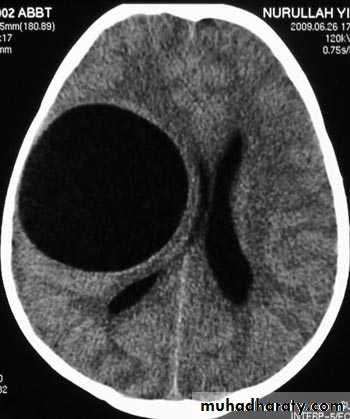

Hydrocephalous

2 types

Obstructive ( non – communicating )

Non –obstructive ( communicating )

No obstruction of the ventricular pathway , but the absorption of the csf at the level of arachnoids' granulation is occluded secondary to lodge by blood clot or inflammatory cell or infection post meningitis most commonly to occur post SAH .

CT Scane